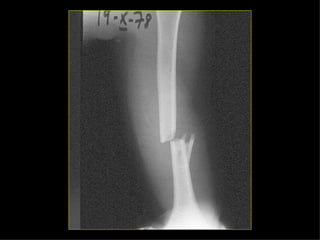

Mecanismo Tensión. Las fracturas son transversales. Rotación. Espirales. Compresión. Característicamente oblicuas. Angulación. Transversas. Angulación más compresión. Genera fractura de dos componentes: transversal y oblicuo (45º). Conminuta. Con múltiples líneas de fracturas.

Mecanismo Tensión. Lasfracturas son transversales. Rotación. Espirales. Compresión. Característicamente oblicuas. Angulación. Transversas. Angulación más compresión. Genera fractura de dos componentes: transversal y oblicuo (45º). Conminuta. Con múltiples líneas de fracturas.